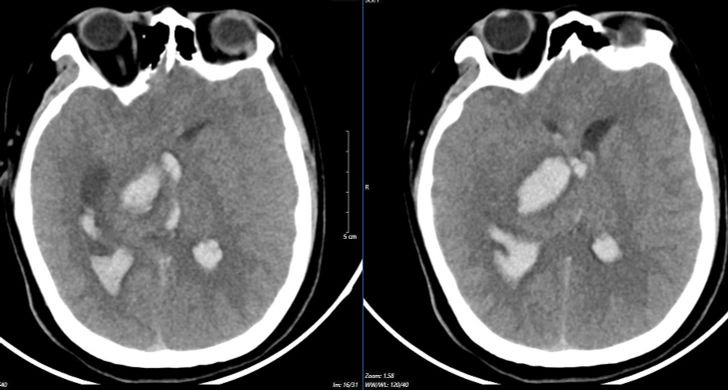

뇌졸중 센터에서 환자의 오른쪽 동공이 확대된 것으로 확인되었습니다. 스캔 결과 뇌동맥류 파열로 인해 뇌에 출혈이 있는 것으로 나타났습니다. 뇌실이 비정상적으로 커지는 합병증이 발생합니다. 체온의 이상 섭씨 39~40도에 달하는 고열이 계속됐다. 뇌혈관 이상은 극도로 위험한 상태였다.

뇌졸중센터에서 집중치료를 받았음에도 불구하고 하지만 환자의 상태는 빠르게 악화됐다. 그리고 심각한 예후를 가지고 있습니다 이틀 간의 응급 치료 끝에 의사들은 그에게 더 이상 생명 유지 장치를 할 수 없다는 통보를 했습니다. 그래서 환자는 집으로 보내졌습니다. 그리고 나중에 사망